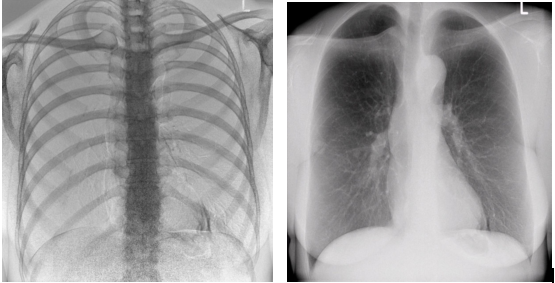

2)圖像質(zhì)量無畸變,無失真

高效動(dòng)態(tài)平板技術(shù),圖像不會(huì)有幾何畸變,提供高分辨率和精確的圖像,為臨床診斷提供精準(zhǔn)依據(jù)。

最高幀速可達(dá)30幀/秒,獲得與靜態(tài)采集相媲美的高清流暢影像;

采用先進(jìn)的脈沖透視技術(shù),呈現(xiàn)更優(yōu)圖像空間分辨率、低對(duì)比度分辨率、灰階范圍,為精準(zhǔn)診斷提供可靠依據(jù)。

4)透視+高清點(diǎn)片

在可視過程或回放過程中,如發(fā)現(xiàn)疑似病灶,可進(jìn)行毫秒級(jí)高清點(diǎn)片,隨時(shí)抓取單幀圖像,精準(zhǔn)捕抓病灶,便于醫(yī)生進(jìn)一步診斷分析,減少誤診,并有助于快速編制報(bào)告。